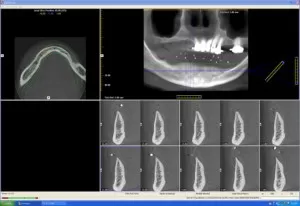

Chụp CT và scan hàm giả bệnh nhân đang đeo

Dựa trên các dữ liệu của phim CT & phần mềm Nobel Clinician để lên kế hoạch điều trị:

Tuy nhiên nhóm bác sỹ nhận thấy sống hàm vùng cằm tại các vị trí răng 32, 35, 42, 45 cần đặt implant không bằng phẳng, nhỏ và nhọn.

Do đó nhóm Bs quyết định phương án: gọt thấp xương hàm vùng cằm để gia tăng kích thước đường kính của các implant và tạo thuận lợi cho phục hình sau này.